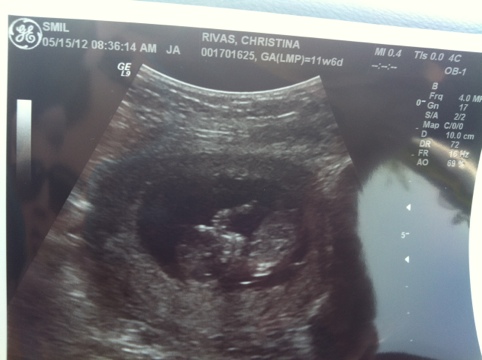

So my baby is 3 1/2 inches long. That’s about the size of a fist, unless you have giant man hands and then it’s about the size of my fist. Take that. I’m also starting to notice a decrease in the crap symptoms from the first trimester. Except for morning sickness because DEAR GOD let’s not let that one go anywhere. I don’t, however, feel liked warmed over ass 100% of the time anymore. It’s only about 43% of the time now. ‘Tis a pregnancy miracle!